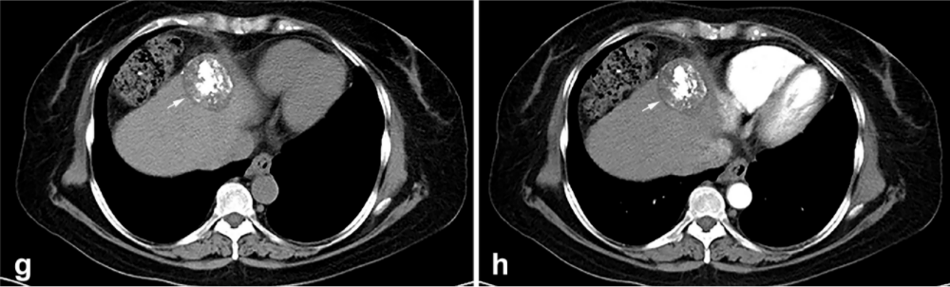

背景:由于一些原因,位于膈肌附近的肿瘤的热消融在技术上具有挑战性。首先,术中计算机扫描和超声检查无法清晰显示射频消融/微波消融切缘。第二,消融过程中不利的针分布和过热可能导致肝包膜破裂,并对膈、肺和心脏造成严重损伤。第三,即使使用人工腹水,仍有9~22%的患者因肝周粘连或肿瘤位置靠近肝表面而导致膈肌热损伤。冷冻消融可能是毗邻膈肌的HCC的一种有前途的治疗方法,因为在消融过程中使用CT和US可以很好地显示肿瘤边缘。尽管一些研究评估了在高危区域使用冷冻消融治疗HCC,但很少有研究针对膈肌临近区域。